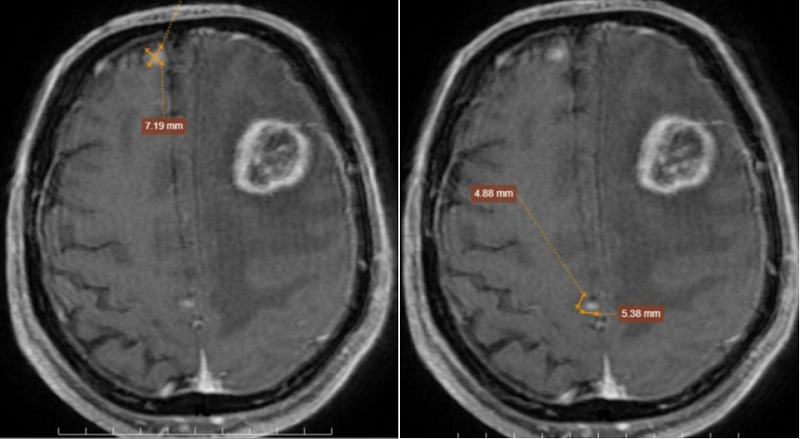

MRI sọ não phát hiện tổn thương ngấm thuốc hai bán cầu và tổn thương màng não

Phát hiện nhiều nốt tổn thương ngấm thuốc hai bán cầu và tổn thương màng não

Trong ca bệnh này, các tổn thương não có số lượng nhiều (4-5 ổ), phân bố ở vùng vỏ và dưới vỏ não, phù não lan rộng và hình ảnh ngấm thuốc dạng viền rõ. Những đặc điểm này phù hợp với u não thứ phát, tức là u di căn từ cơ quan khác, thay vì u não nguyên phát.